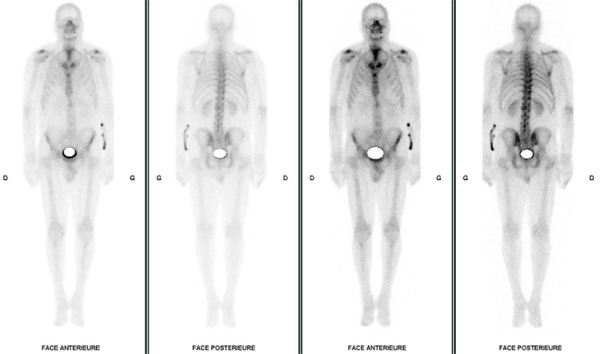

- Scintigraphie osseuse

Scintigraphie osseuse

Figure 8 : score de PERUGUINI : 0 - Scintigraphie normale